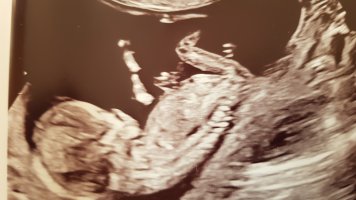

det burde være veldig tydelig så langt på vei, men bilde er ikke det beste. har du flere bilder?

Oul i dag viste jente! So vi hadde rett!hvis man skal gjette ut i fra disse bildene ville jeg ha tippet litt mer sannsynlighet for jente.